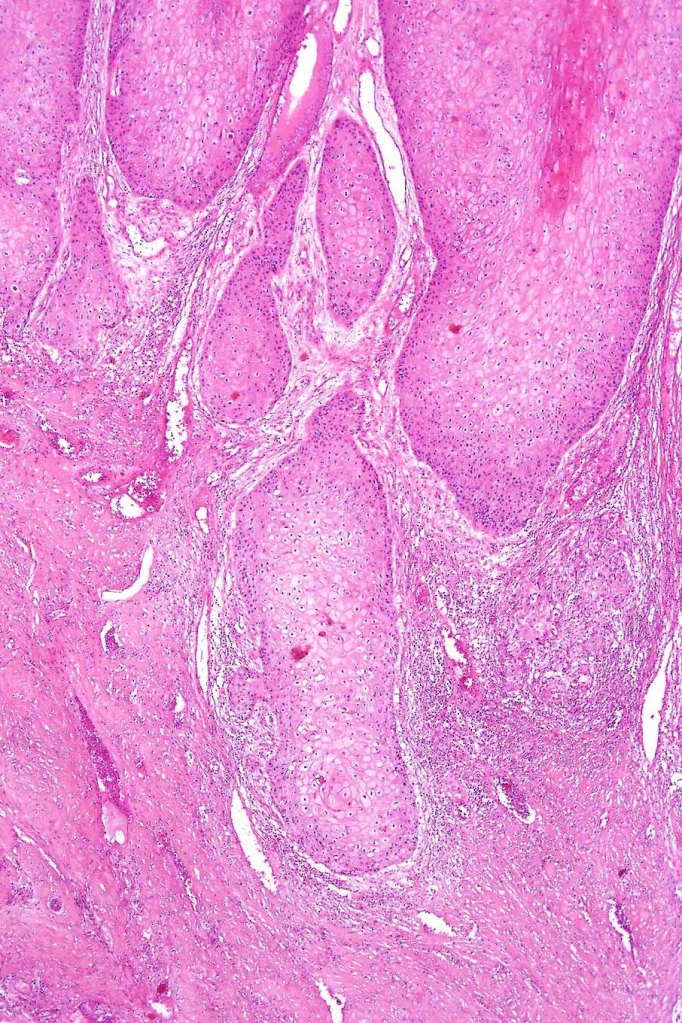

•Deeply penetrating bulbous processes with a pushing rather than infiltrating lower border

•Well differentiated epithelium characteristically having a ground glass appearance

•Marked tumor necrosis

•Intraepithelial abscesses

•Basally located mitoses